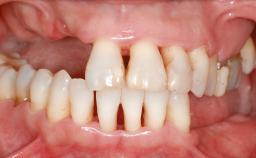

A 45-year-old woman with a completely edentulous maxilla was referred to evaluate the possibility of rehabilitation with an implant-supported prosthesis. This patient was healthy and a non-smoker. She had been wearing a maxillary complete denture opposing a natural mandibular dentition since her twenties. This situation had resulted in progressive resorption of the alveolar ridge, repeatedly creating a need for relining the denture. Twenty years later, despite multiple adaptations and the use of “glues” the denture was unstable and causing the patient psychological and functional discomfort.

Bone Volume Horizontally and vertically sufficient Horizontally deficient Deficient vertically or deficient vertically AND horizontally

Bone Volume Deficient vertically or deficient vertically AND horizontally